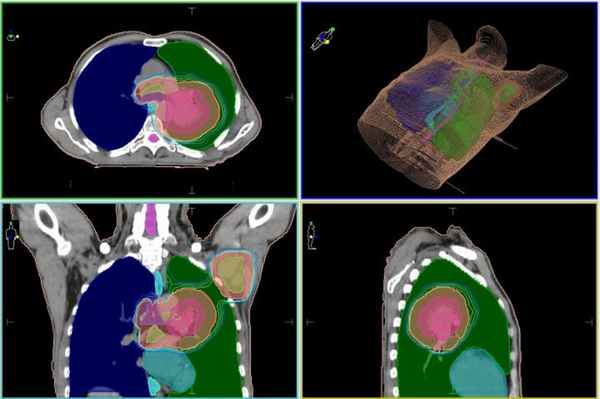

При большей распространенности процесса в качестве радикального метода лечения мезотелиомы чаще всего применяется хирургическое вмешательство, которое комбинируется с химиотерапией и лучевой терапией.

Лечение мезотелиомы плевры на современном лийнейном ускорителе в Киеве: план лечения. Высокая доза ионизирующего излучения после проведения хирургического удаления опухоли и пораженных элементов лимфатической системы будет подведена внутрь двух зон, выделенных розовым контуром

В каждом отдельном случае принимается индивидуальная тактика лечения на основе международных протоколов, которую определяет междисциплинарный консилиум врачей.